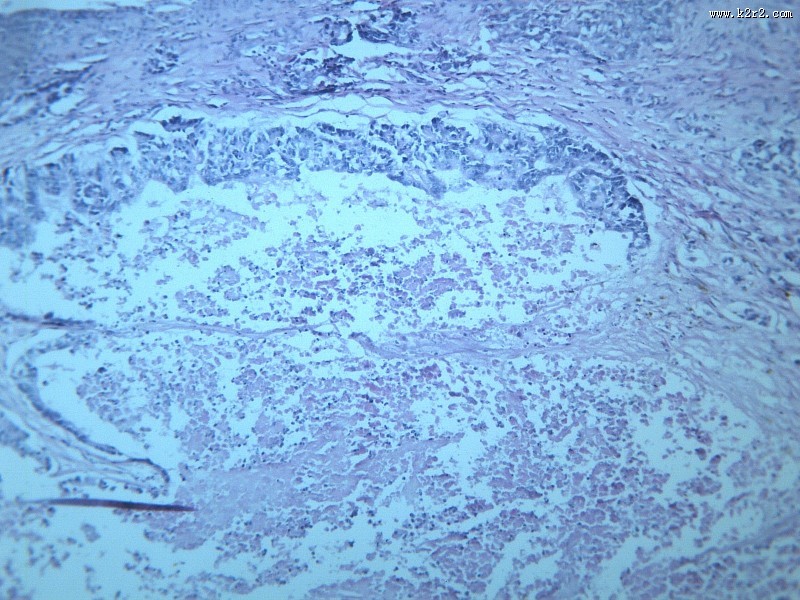

腺癌肝转移大全 - 第10张

腺癌肝转移大全

淋巴结内转移癌

腺癌

腺癌肝转移